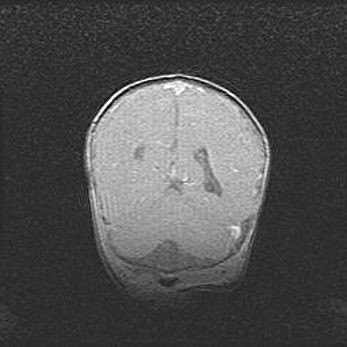

Наружная гидроцефалия с возможной атрофией височных областей.

Возраст: 28 дней

Вес: 3670 г

Пол: мужской

Окружность головы: 38 см

Срок гестации: 40 недель

Гидроцефалия головного мозга у новорожденных – это заболевание, которое характеризуется скоплением избыточного количества спинномозговой жидкости в желудочковой системе головного мозга в результате затруднения её перемещения от места выработки к месту поглощения в кровеносную систему или вследствие нарушения абсорбции. При открытой наружной форме гидроцефалии у новорожденных расширяются и переполняются субарахноидные пространства.

При нормотензивных  формах,  которые,  как  правило,  являются  следствием  перенесенных ишемических  повреждений  паренхимы  мозга,  возможно  сочетание микроцефалии  с нормотензивной гидроцефалией. В основе данных изменений лежит атрофия больших полушарий с преимущественной  локализацией  в  лобно-височных  областях.